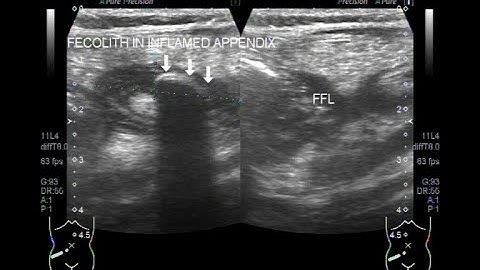

Ultrasound video showing inflamed gangrenous appendix, intramural gas shadows in base of appendix